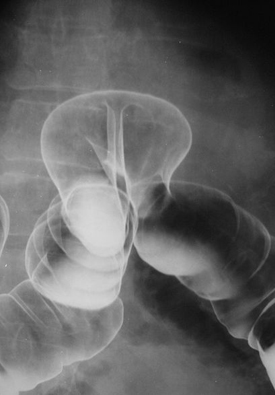

L'enteroclyse : Par une sonde duodenale

placee en among de angle de Treizt . le produit de contrast

se deverse dans intestin grele . En premier temps l'intestin

est opacifiee par baryum uniquement . Au deuxieme temps avec

un peut de air intille au de dans , un "effet de double de

contrast " est obtenue . Ce qui permet une analyse plus fine

de la portion de l'intestin observe . Cette technique est

plus presise pour l'etude a interieure de la portion

precedent de l'intestin grele .

L'enteroclyse de angle de Treizt ,

jejunum , et une parties superieure de l'ntestin

|

Images de

l'estomac et partie superieure de l'intestin en

double de contrast . |